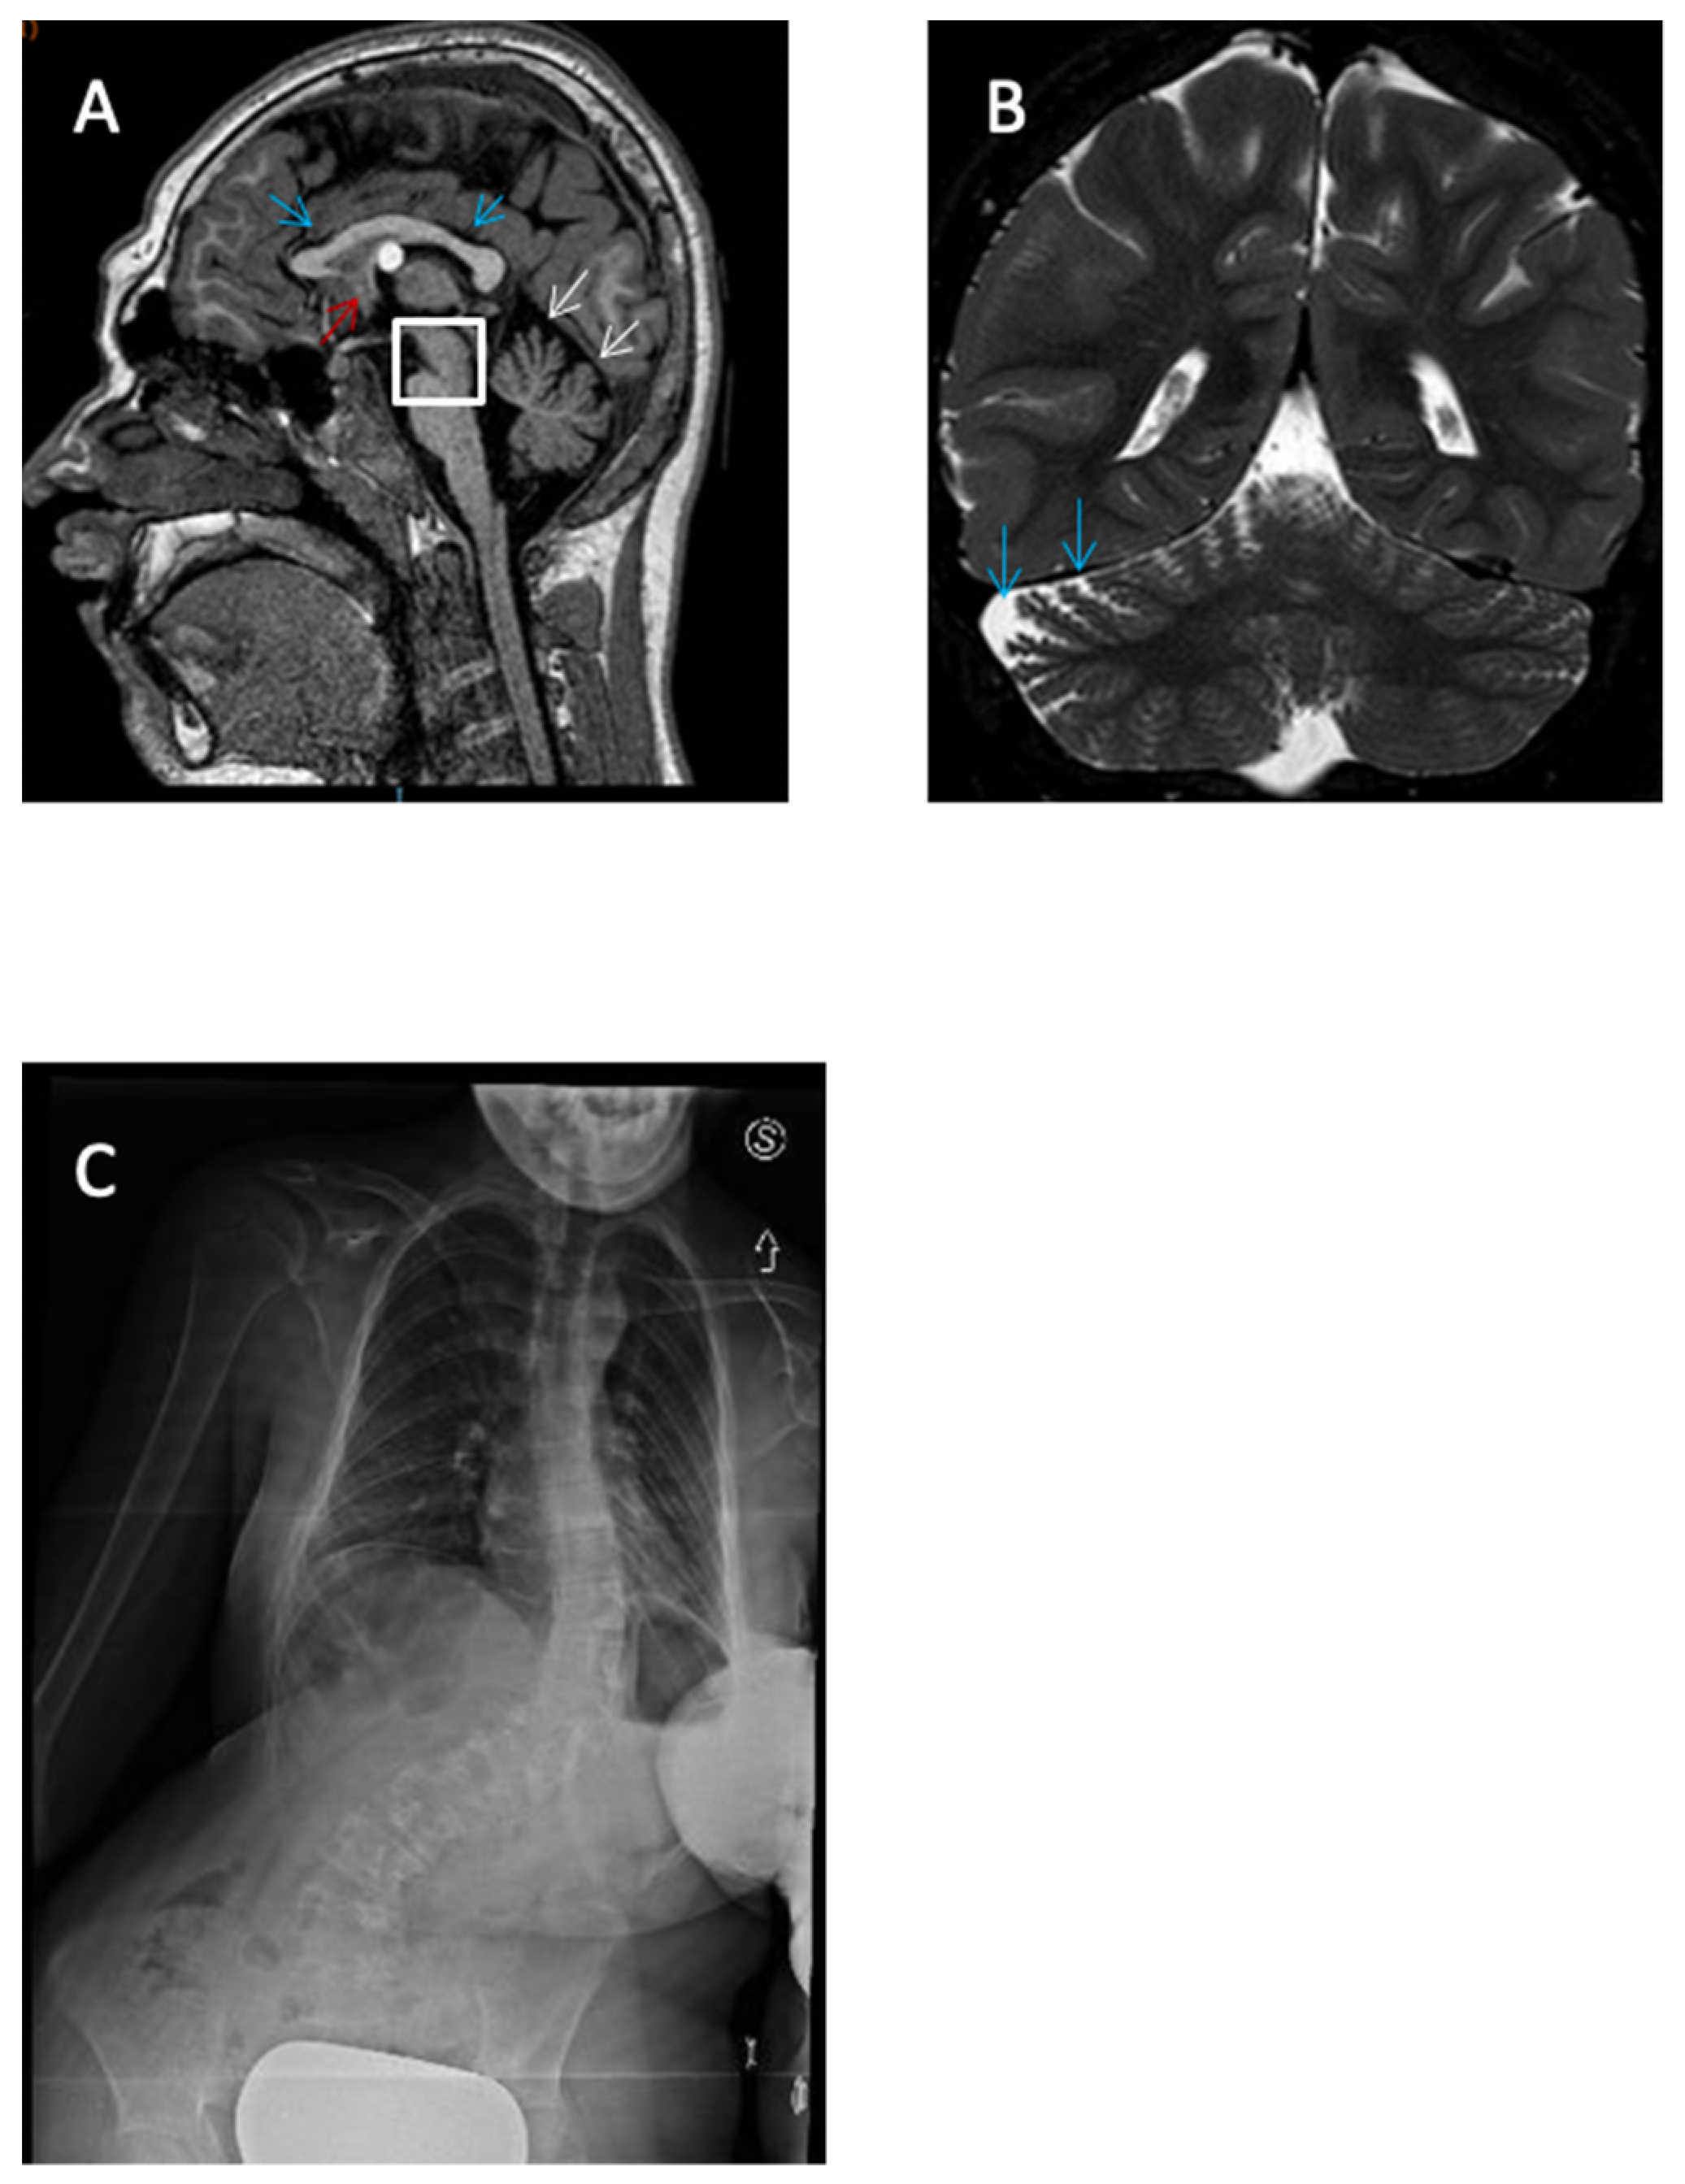

Magnetic Resonance Imaging (MRI), on the other hand, was performed in the cases of eight patients, and returned normal results in five of them (62.5%). Patient 3 presented hypoplasia of the cerebellar worm, delayed myelination, and increased size of cisterna magna. Patient 6 displayed adipose transformation of the Filum Terminale, a colloid cyst of the third ventricle, hypoplasia of the corpus callosum and pons, and enlargement of the cerebrospinal fluid spaces (Figure 4). Finally, patient 7 showed gyral simplification and delayed myelination.

Figure 4.

Imaging findings of patient N 6: (A,B) Brain MRI showing low spinal cord with adipose transformation of the Filum Terminale, colloid cyst of the third ventricle (A, red arrow), microcephaly, hypoplasia of the corpus callosum and pons (A, blue arrows), and enlargement of the CSF (A, white arrows; B, Blue arrows). (C) RX showing severe scoliosis.

3.6. PATIENT 6

Patient 6 is an 18-year-old girl with profound intellectual disability, motor delay, and severe hypotonia. She started to walk at age 4. She said her first words at 5 years of age and communicates only through short sequences. At 8 months old, she presented febrile seizures and was treated with valproate for 9 years with good seizure control. The brain MRI showed low-lying spinal cord with adipose transformation of the Filum Terminale, colloid cyst of the third ventricle, microcephaly, hypoplasia of the corpus callosum and pons, and enlargement of the cerebrospinal fluid spaces. Dysmorphic features included a depressed and receding forehead, hypertelorism, prominent glabella, low-placed ears, short filter, small and teeth that have undergone diastasis and retrognathia (Figure 1). Other findings included lymphedema, severe scoliosis, long tapered fingers, and cardiac anomalies such as IM and IT.

She showed a heterozygous missense in the frame variant on exon 2, which causes the deletion of only one amino acid (nm_001320:c.181_183del, p.Glu61del, p.Glu61del).